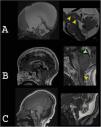

Macrocephaly is a clinical term defined as an occipitofrontal circumference more than two standard deviations above the mean. It is present in 5% of children and is a common indication for imaging studies. There are multiple causes of macrocephaly; most of them are benign. Nevertheless, in some cases, macrocephaly is the clinical manifestation of a condition that requires timely medical and/or surgical treatment. The importance of imaging studies lies in identifying the patients who would benefit from treatment. Children with macrocephaly associated with neurologic alterations, neurocutaneous stigmata, delayed development, or rapid increase of the circumference have a greater risk of having disease. By contrast, parental macrocephaly is predictive of a benign condition. Limiting imaging studies to patients with increased risk makes it possible to optimize resources and reduce unnecessary exposure to tests.